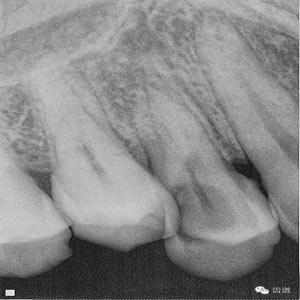

檢查:14遠(yuǎn)中鄰頜面探及齲壞至牙本質(zhì)深 層,穿髓。探-,冷-,叩-。松動(dòng)-。牙齦無(wú)紅腫,未探及牙周袋。

數(shù)碼攝影x片顯示:14遠(yuǎn)中鄰頜面暗影,穿髓。根尖暗影。無(wú)牙周膜增寬。